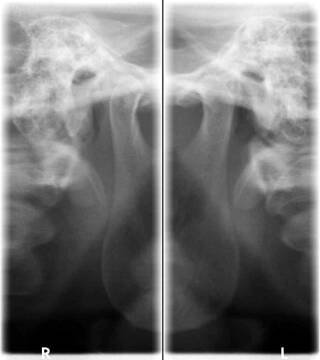

- zdjęcia panoramiczne wycinkowe stawów skroniowo_żuchwowych

Zdjęcia pantomograficzne wykonane nowoczesnym aparatem RTG umożliwiają ocenę stawów skroniowo-żuchwowych oraz RTG zatok szczękowych.

RTG pantomograficzne wykonane w klinice stomatologicznej ATJ można poszerzyć RTG stawów skroniowo-żuchwowych, RTG zatok szczękowych czy dokładny rentgen zęba.